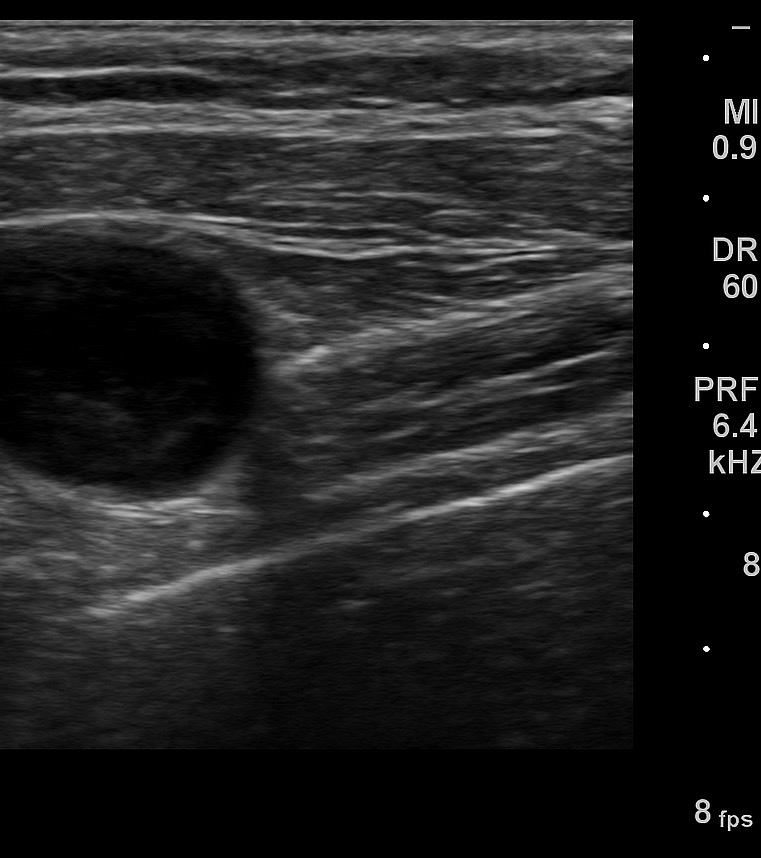

Ecografía musculoesquelética: lesión anecoica redondeada de aproximadamente 2 cm, con patrón yin-yang en Doppler color y flujo turbulento en Doppler espectral, compatible con pseudoaneurisma dependiente de rama arterial axilar superficial. No datos de bursitis, absceso o hematoma no vascularizado.